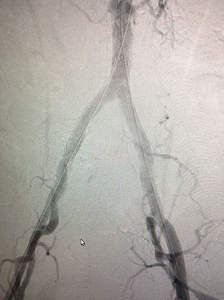

В рамках мастер-класса пятерым пациентам Клиники была выполнена реканализация и последующее стентирование терминального отдела брюшной аорты с выходом в подвздошные артерии.